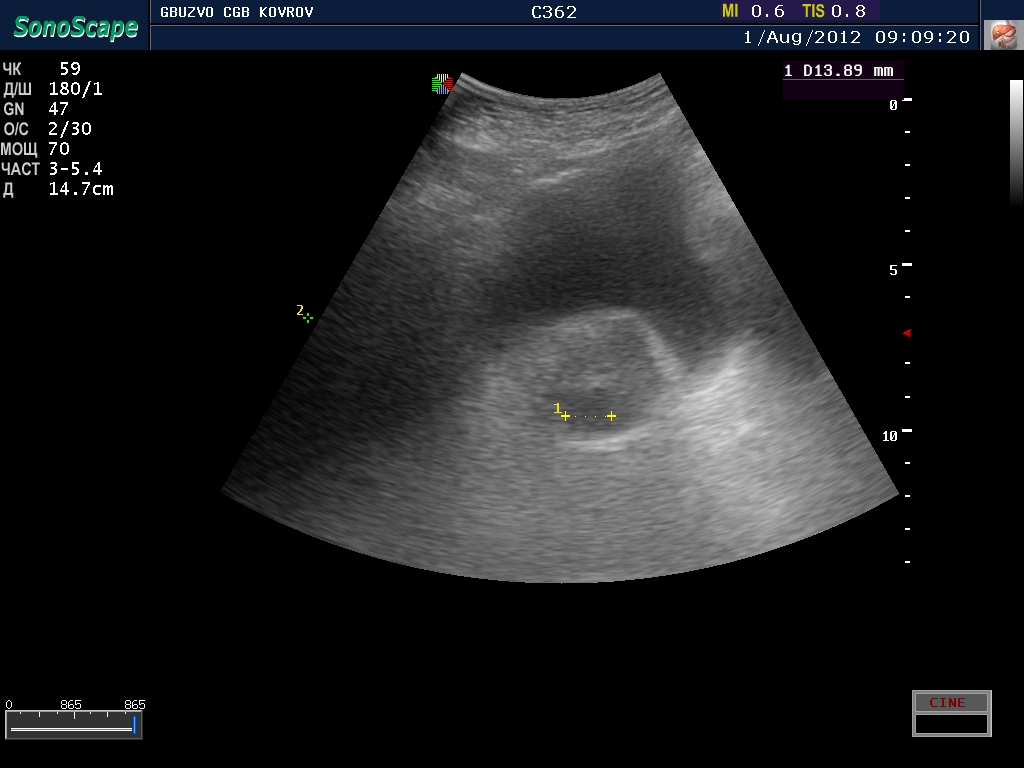

В простате лоцируется гипоэхогенное округлое образование - вопрос - как трактовать?

простатическая часть уретры или очаг?

V-мочевого пузыря 450 мл , стенка 7 мм в ней псведодивертикулы Vост - 380мл, V простаты 36 мл

Вроде как клиническая проблема есть. Сначала была у меня тенденция трактовать это как очаг, но потом рука дрогнула и я решил не заметить сей факт..норма?